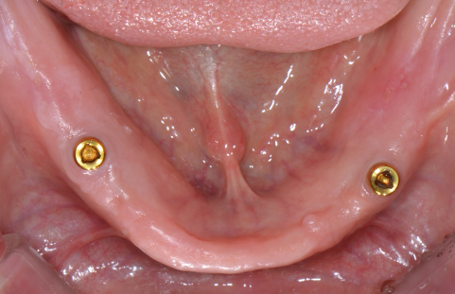

그냥 틀니는 유지력과 안정성이 떨어지기 때문에

임플란트를 2개만 심을 수 있다면 여기에 유지력을 부여할 수 있는 단추를 달고

틀니 내면에도 이를 붙잡을 수 있는 소켓을 연결함으로써

훨씬 사용하시기 편리한 틀니를 제작해 볼 수 있습니다.

왼쪽은 입 안을 보여주는 사진이고 오른쪽은 틀니 내면을 촬영한 사진입니다.